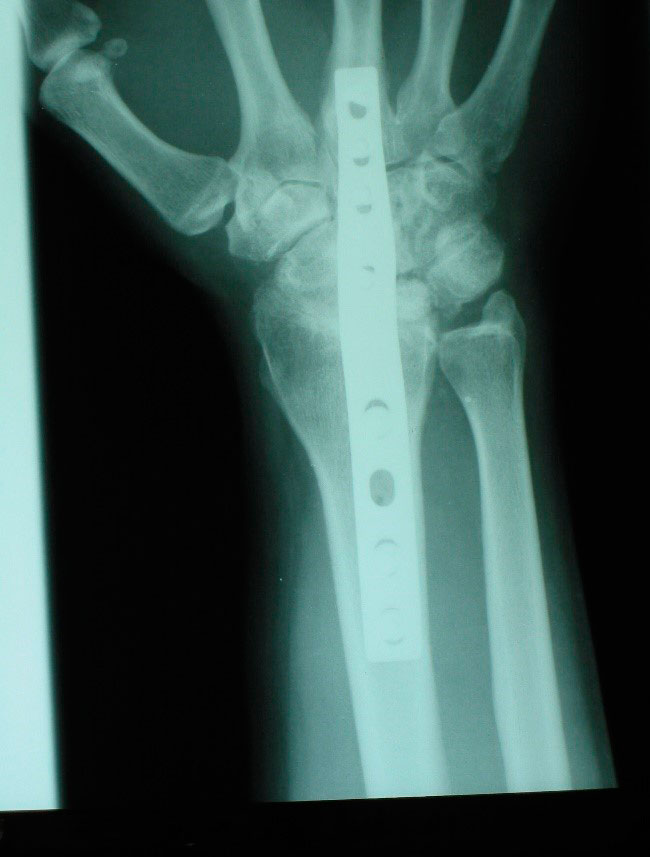

Nosotros realizamos una osteotomía de valguización del radio que consiste en extraer una cuña de base radial y se fija con una placa (figura 9).

La artrodesis total de muñeca como tratamiento de la enfermedad de Kienböck consiste en fusionar el radio con el carpo, de tal manera que se pierde la extensión y flexión de la muñeca (a menudo muy disminuida en los estadios avanzados de Kienböck). Está indicada en pacientes con alta demanda funcional en estadios IIIB y IV. Nosotros optamos en estos casos optamos por esta técnica debido a los buenos resultados en la disminución del dolor y en la ganancia de fuerza (figura 14).

Figura 14: artrodesis total de muñeca sintetizada con placa